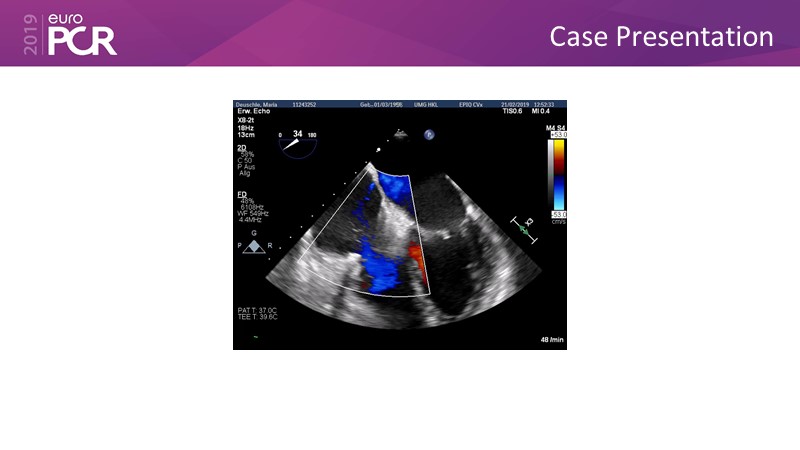

Addressing tricuspid regurgitation with annular reduction: the Cardioband tricuspid system

Consult this session to understand how patients with tricuspid regurgitation and annular dilatation can benefit from Cardioband system...